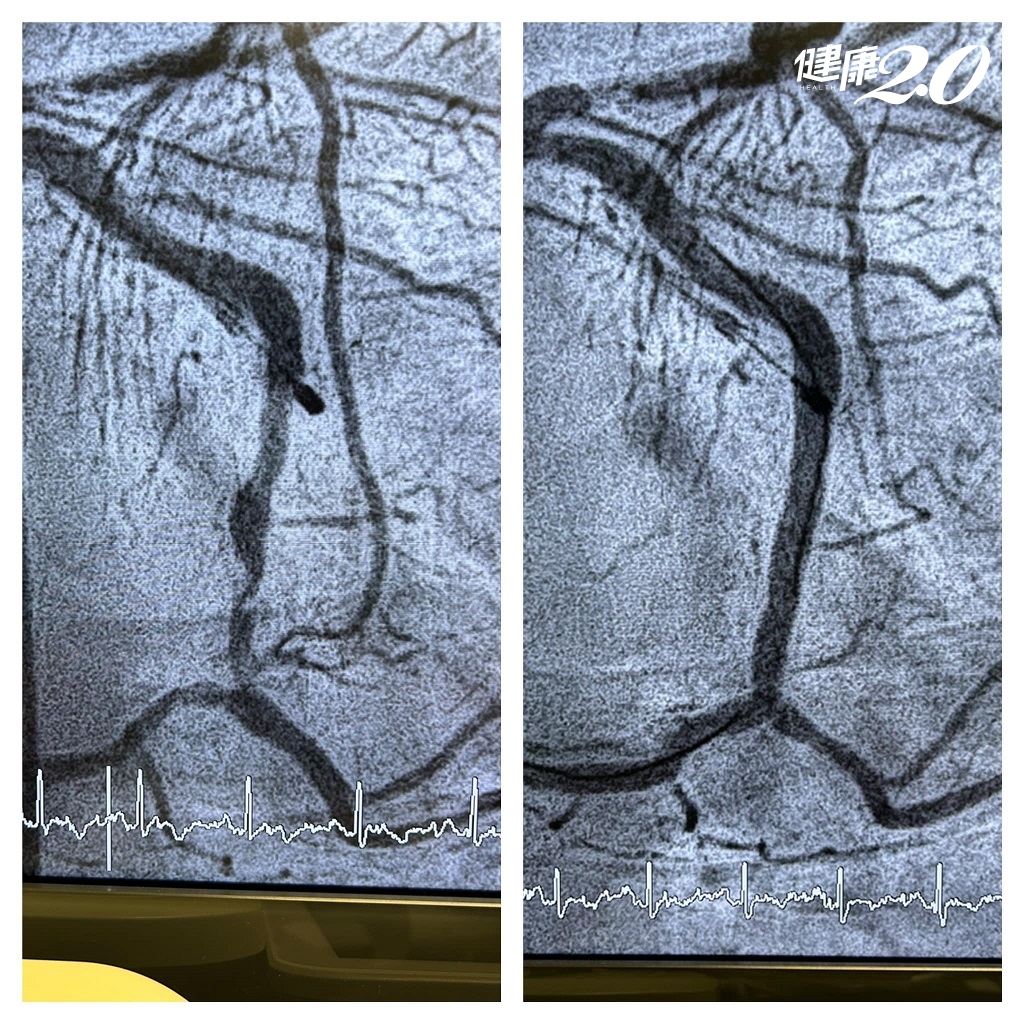

陳冠任醫師表示,當下立刻安排做心電圖和胸部X光,驚見心電圖竟然呈現「急性心肌梗塞」,不緊急做心導管手術會有生命危險,術後發現有2條血管通通都塞住,狹窄超過90%以上,若不打通隨時會有猝死的可能,幸好手術順利,目前症狀改善、血管已暢通。

▲病患的2條血管術前(左)阻塞,幸好術後(右)已暢通。(圖片/陳冠任醫師提供)